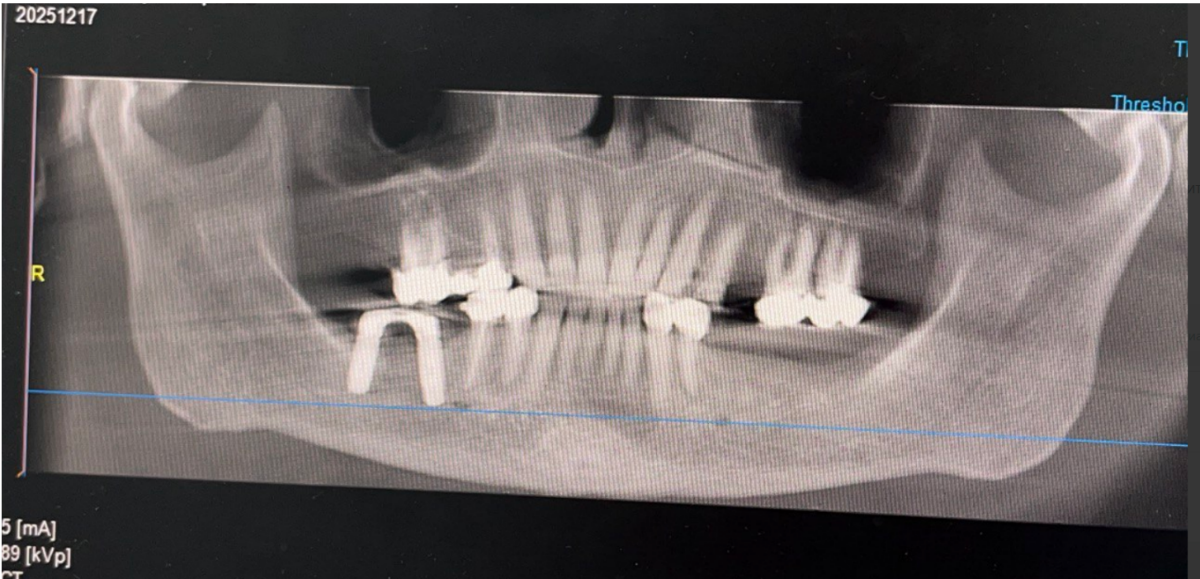

Женщина 74 года. Установила бюгельный протез на нижнюю челюсть 2 года назад, который крепится справа на коронке с замком, а слева на заглушенных имплантатах. Имплантатам свыше 15 лет, на консультациях сказали, что их больше нельзя использовать для протезирования, кость плохая, только удаление. Ортопед принял решение имплантаты не удалять, а использовать их в систему для бюгельного протеза. Недавно под протезом стал побаливать зуб при надкусывании. Сделала КТ. Справа на зубе под коронкой с замком, на котором держится эта конструкция, образовалась гранулема. Теперь встал вопрос: как быть. Почему образовалась гранулема? До протезирования ничего не было, могла такая конструкция вызвать воспаление? Можно ли вылечить данный зуб? В клинике, где делали КТ, предложили, как вариант, высверлить в коронке дырку и попытаться пролечить зуб.  Поможет ли это? Или снимать коронку, как полагается, и лечить классическим методом? Что можно сделать в данном случае? Или уже ничего не поможет? Оставить всё как есть до тех пор, пока зуб окончательно не разболится и просто его удалить?